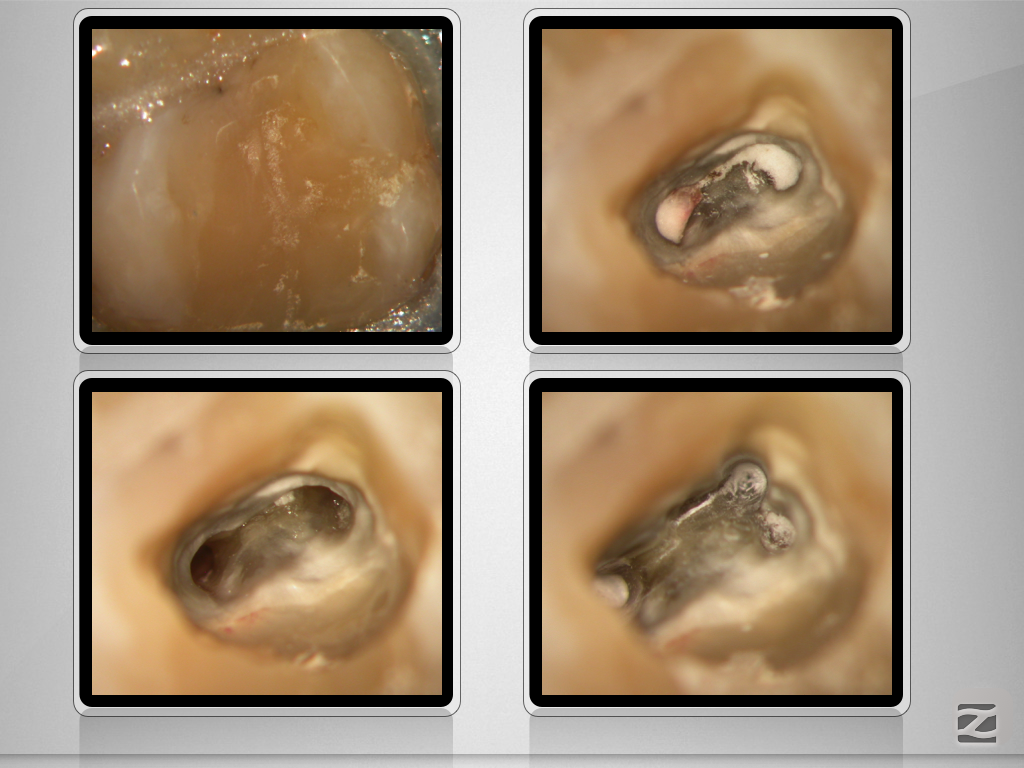

17D.013

Gewusst, wo’s lang geht.